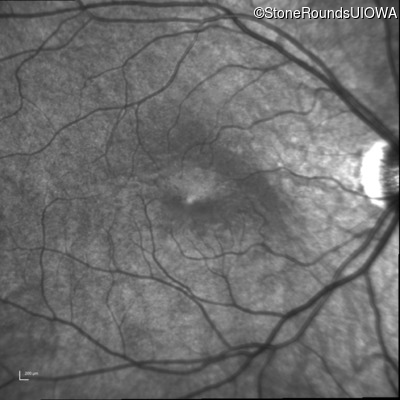

Infrared Fundus Photograph - Right - 20/40 +1

Exemplar